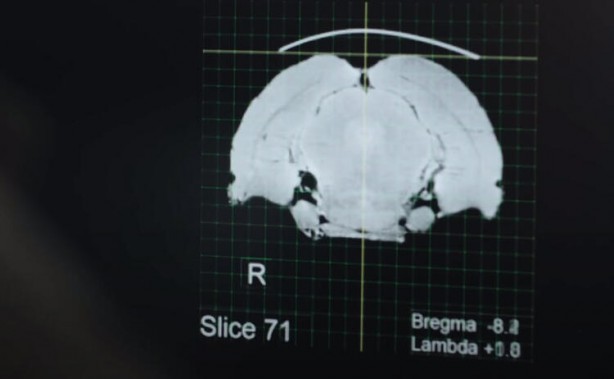

Çip takılan bir domuzun beyin sinyalleri ekranlara aktarılarak, canlı yayında takip edildi.